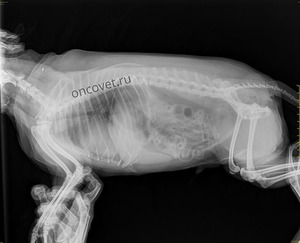

Методы диагностики

Так как клиническая симптоматика может развиваться в единичных случаях, а в основном слабо либо долгое время вовсе не показывать себя, то подтверждение диагноза «коллапс трахеи» всегда требует осуществления более тщательного осмотра с использованием нового оборудования.

Для начала стоит провести пальпацию трахеи собаки. Если болезнь всё-таки имеется, то форма трахеи очень сильно деформирована — на стенке в это время образуется жёлоб либо же сильное уплотнение.

Диагностика у животного может быть затруднённой. Держать питомца на одном месте и поймать время его вдоха-выдоха в большинстве случаев очень сложно. В некоторых случаях собака нуждается во введении успокоительного средства и бариевой кашицы, лишь таким способом она приходит в себя и становится спокойнее. Иногда осуществляют забор ткани трахеи для определения возбудителя болезни и анализа крови на чувствительность к препаратам-антибиотикам.

Время от времени стоит привозить собаку в ветеринарную клинику на эндоскопию и рентгенологическое обследование, чтобы внимательно следить за имплантом или стентом.

Диагностика коллапса трахеи обычно включает физический осмотр ветеринаром, прослушивание дыхательных звуков и рентгенографию грудной клетки. В некоторых случаях может потребоваться бронхоскопия для визуализации трахеи и оценки степени коллапса.